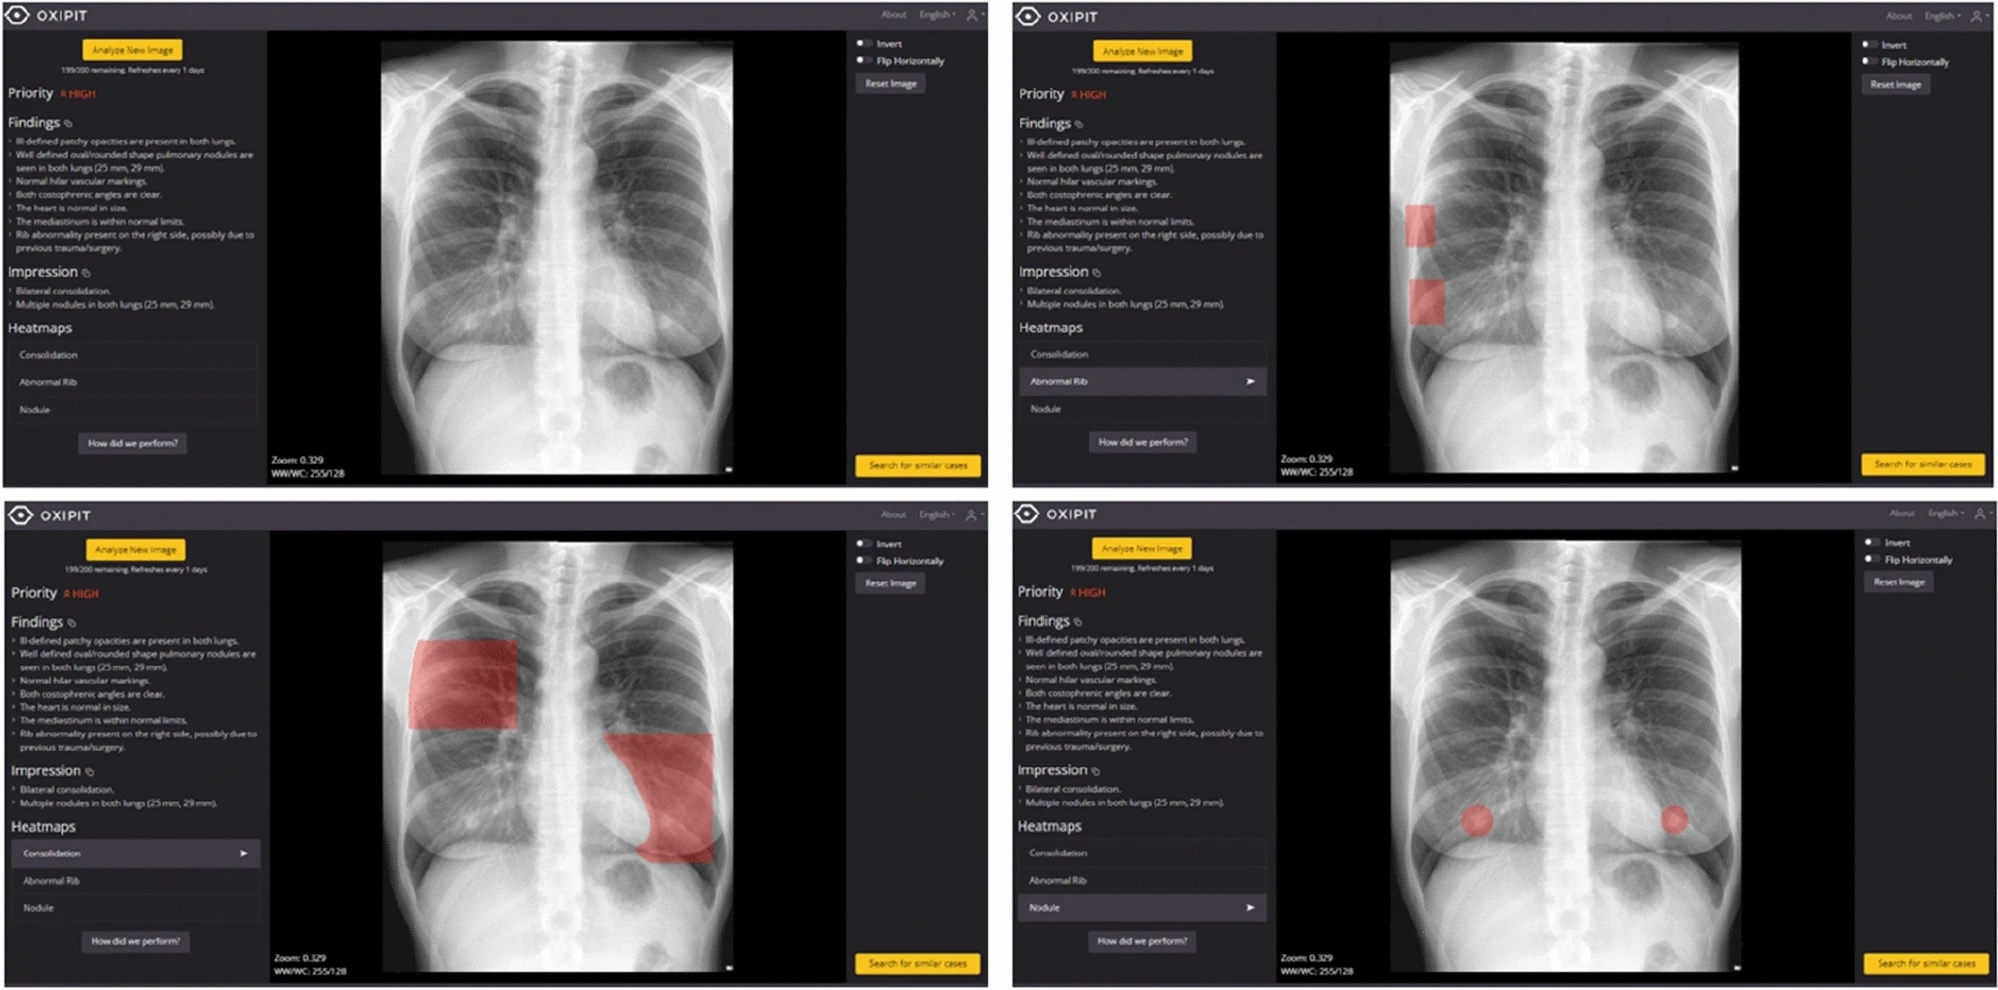

Aside from our ECR coverage, it appears that researchers are calling for more “real-world” studies of AI algorithms designed for interpreting chest x-rays. Recently, a group in Spain tested a product called ChestEye (approved in the European Union in 2019) and found it provided less than what’s required for clinical implementation.